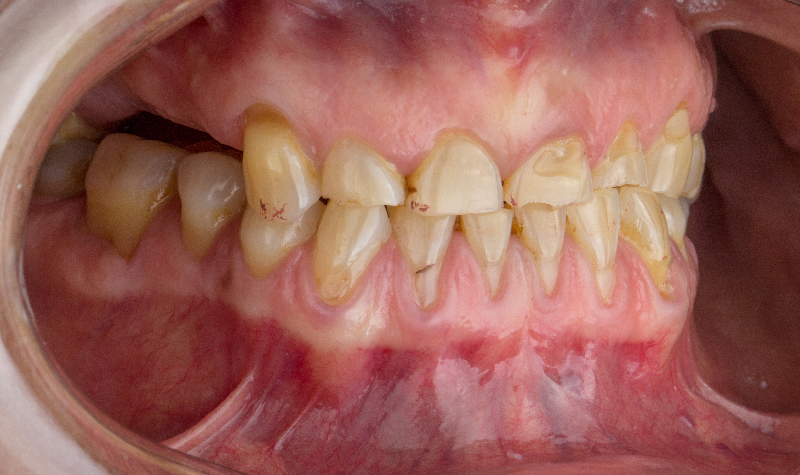

Rehabilitación Oral total con cerámicas sobre dientes e implantes.

Rehabilitación oral total de alta complejidad con cerámicas sobre dientes e implantes.